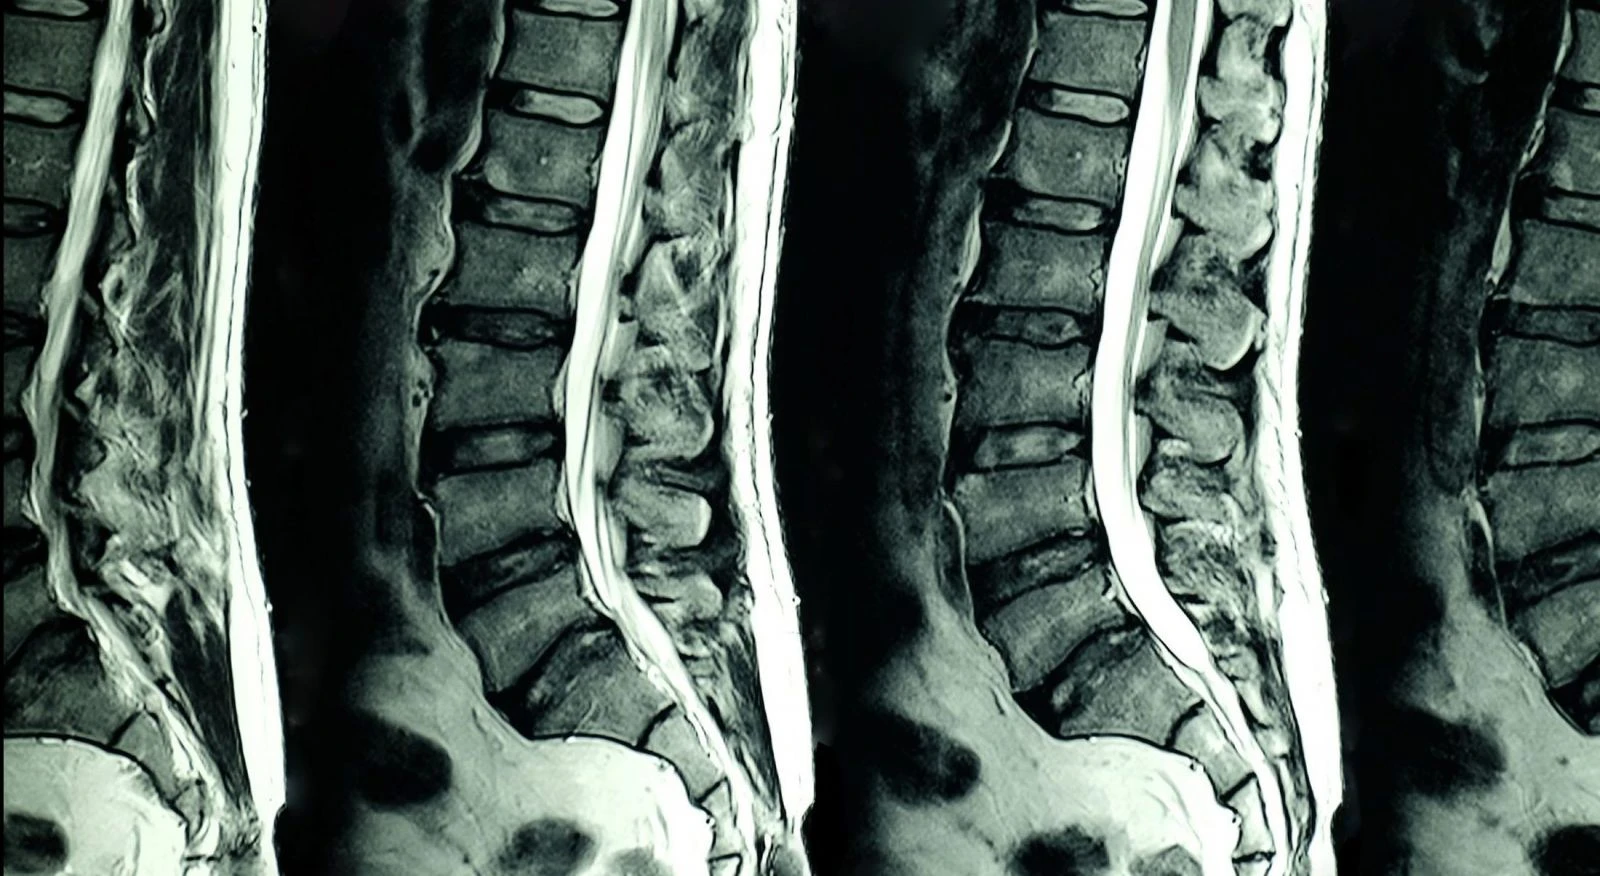

Normal yaşlanma sürecinde diskin ortasındaki su içeriği azalır ve disk yassılaşır. İleri durumda dejenere disk içindeki jel kıvamlı içerik dışarı taşabilir ve "annulus" denen çevresindeki halkavarî yapıya baskı yaparak ağrıya sebep olur. Annulustaki çatlaklar ve yırtıklar da ağrı kaynağı olabilir.